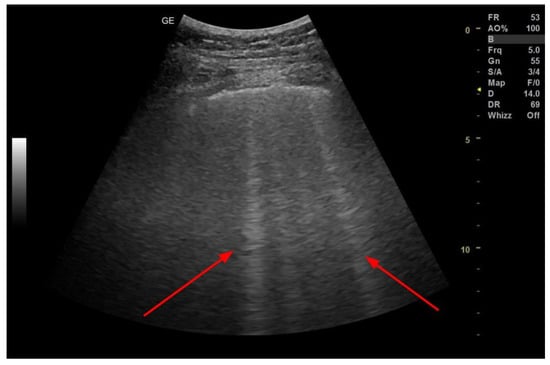

3.3. Pleural Effusion

- Hassan, M.; Rizk, R.; Essam, H.; Abouelnour, A. Validation of Equations for Pleural Effusion Volume Estimation by Ultrasonography. J. Ultrasound 2017, 20, 267–271. [Google Scholar] [CrossRef]

- Laursen, C.B.; Clive, A.; Hallifax, R.; Pietersen, P.I.; Asciak, R.; Davidsen, J.R.; Bhatnagar, R.; Bedawi, E.O.; Jacobsen, N.; Coleman, C.; et al. European Respiratory Society Statement on Thoracic Ultrasound. Eur. Respir. J. 2021, 57. [Google Scholar] [CrossRef]

- Grimberg, A.; Shigueoka, D.C.; Atallah, A.N.; Ajzen, S.; Iared, W. Diagnostic Accuracy of Sonography for Pleural Effusion: Systematic Review. Sao Paulo Med. J. 2010, 128, 90–95. [Google Scholar] [CrossRef] [PubMed]